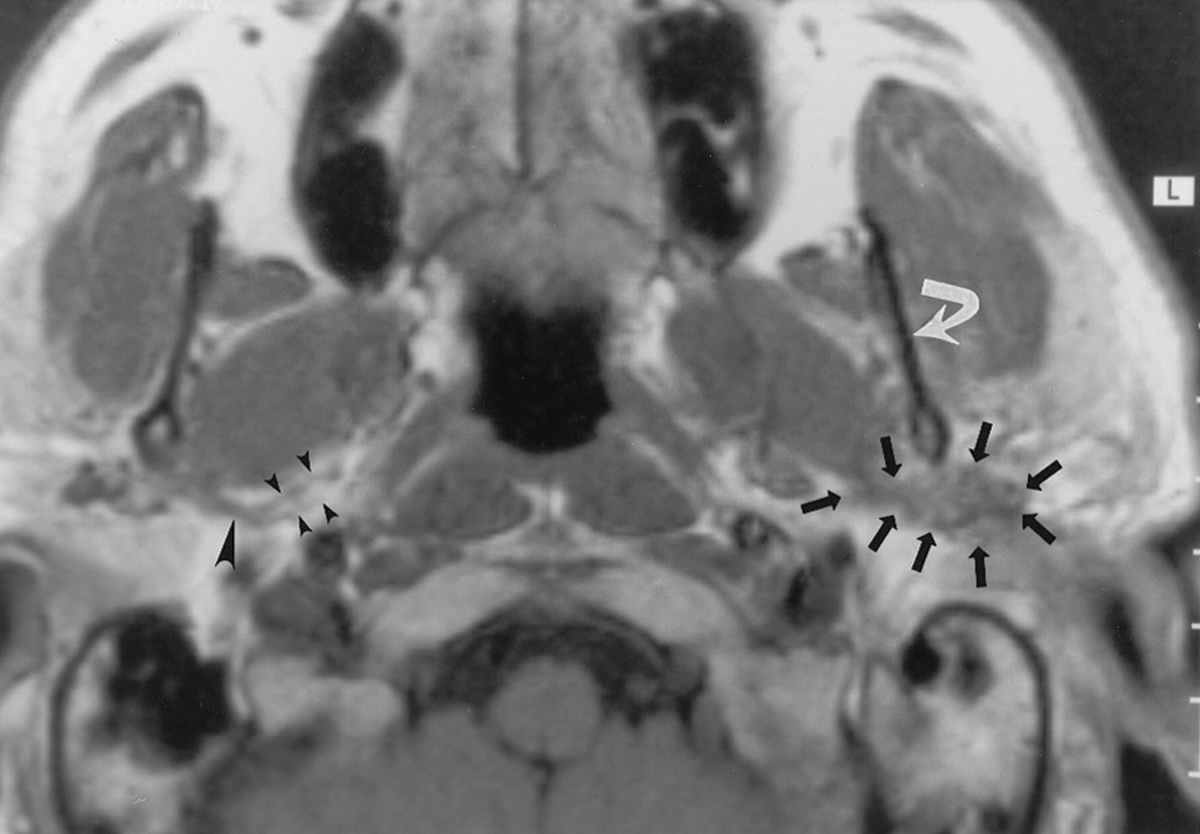

Hemitongue denervation changes (edema, enhancement, and/or fatty change, straight border down the midline) are an important clue to involvement of the hypoglossal nerve

Nasopharyngeal carcinoma can directly extend to the skull base including the hypoglossal canal. These cases won't be subtle - you don't really need a fat pad to help you here.

http://doi.org/10.1007/s003300050492